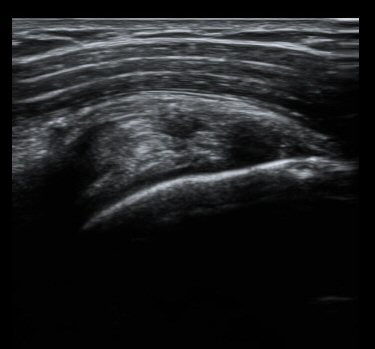

ÃÊÀ½ÆÄ °Ë»ç

ȸÀü±Ù°³°£°Ý Ⱦ´Ü¸é°Ë»ç¿¡¼­ Á¡¾×³¶³» ¼ö¾×Àú·ù°¡ °üÂûµÈ´Ù(±×¸² 1). ÀÌµÎ¹Ú±Ù°Ç °í¶û¿¡¼­´Â ƯÀÌ ¼Ò°ßÀ» º¸ÀÌÁö ¾Ê´Â´Ù(±×¸² 2). ȸÀü±Ù°³°£°Ý ³»Ãø¿¡¼­ °ß°©ÇϱٰÇÀÇ ÆÄ¿­°ú Á¡¾×³¶³» ¼ö¾×Àú·ù°¡ °üÂûµÈ´Ù(±×¸² 3, 4). ±Ø»ó°Ç Ⱦ´Ü